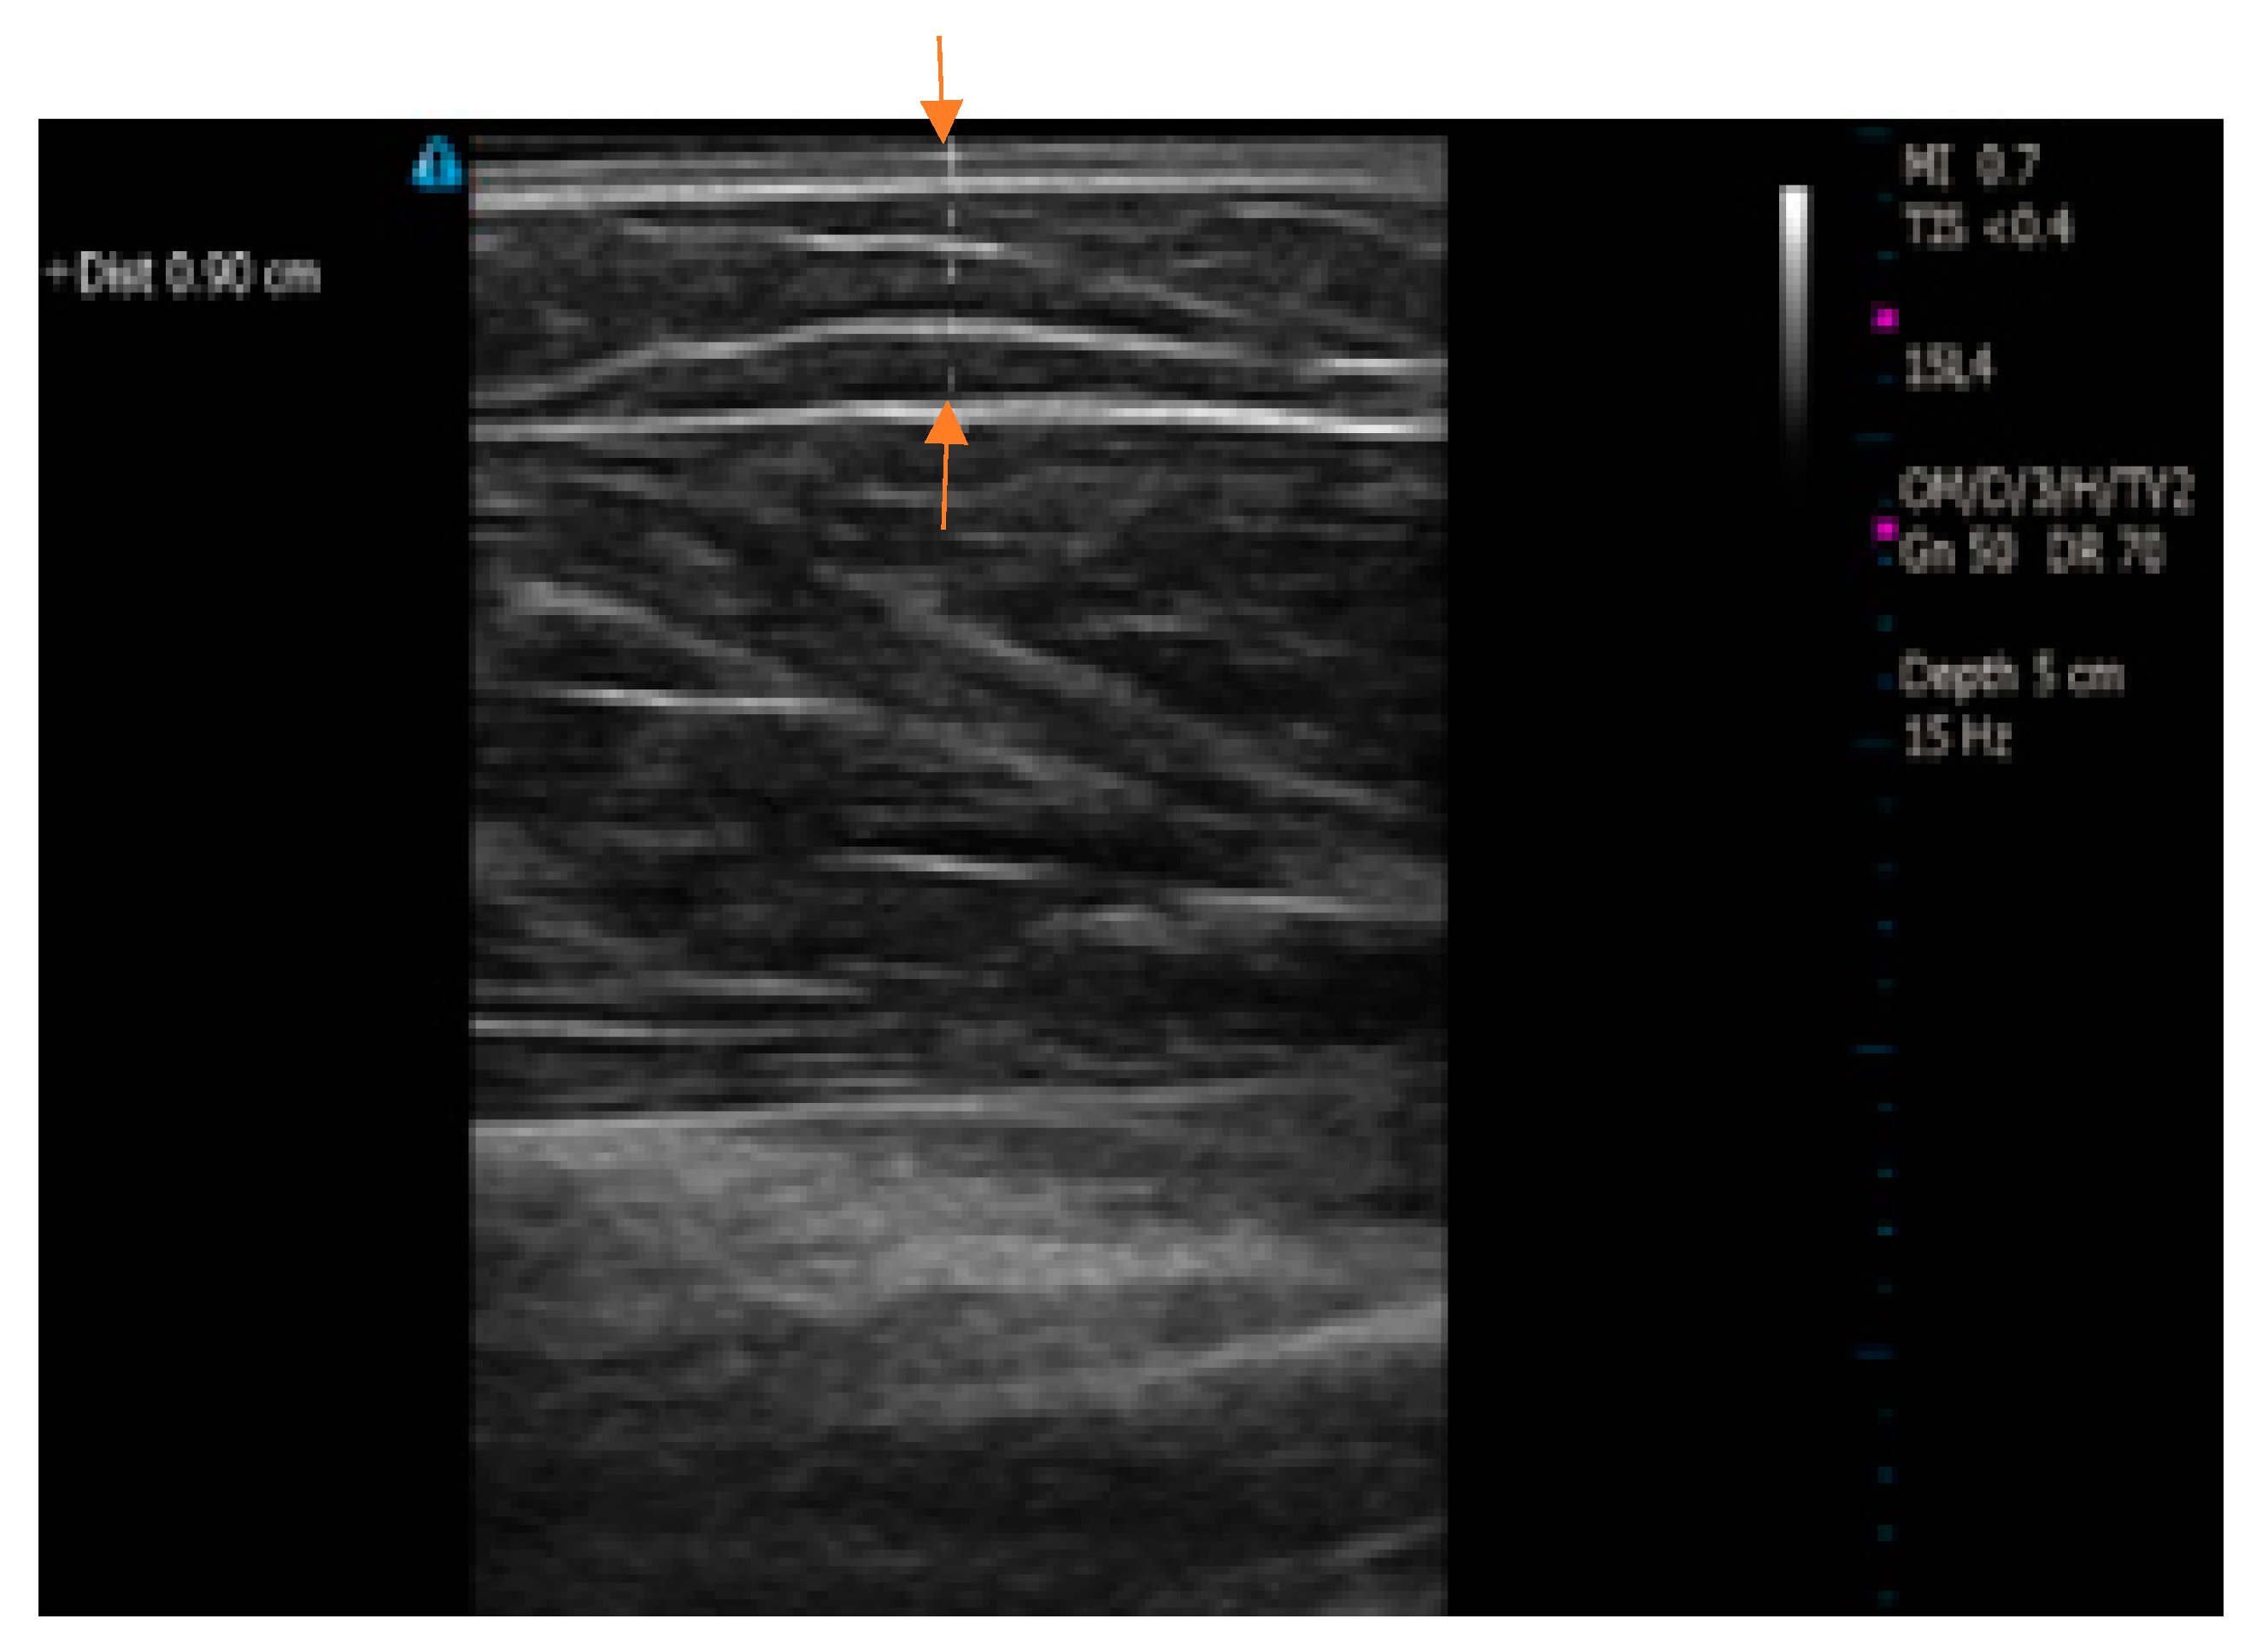

Figure 3 illustrates the process of ultrasound imaging for measuring the fat thickness of individual subjects. The Terason t3200 B-Mode Portable Ultrasound (Terason, Burlington, MA, USA) was utilized to estimate skin-fat thickness. The ultrasound imaging was only applied to that area of the arm that was previously covered by the electrode setup while measuring the skin-fat thickness of the subject. In practice, SF thickness is not uniform along the length of the arm. In order to compensate for the variability, two measurements were taken at the two far ends, one at the approximate middle of the desired zone, and the average of these three measurements was recorded as the SF thickness for the individual subjects in this study.

Figure 3. Ultrasound imaging for the measurement of subcutaneous fat thickness. Arrows show the measured skin-fat thickness.